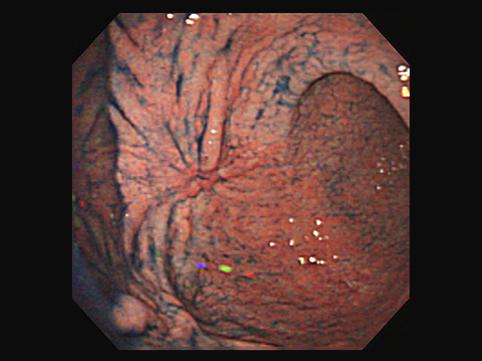

疾病(病理主体)的分类恶性上皮性肿瘤/腺癌

部位(按器官分)胃(部位)/胃角

检查方法内窥镜

肿瘤的肉眼分类0型(表在型)/IIc型(IIc)

肿瘤最大直径30~34

肿瘤的深度m